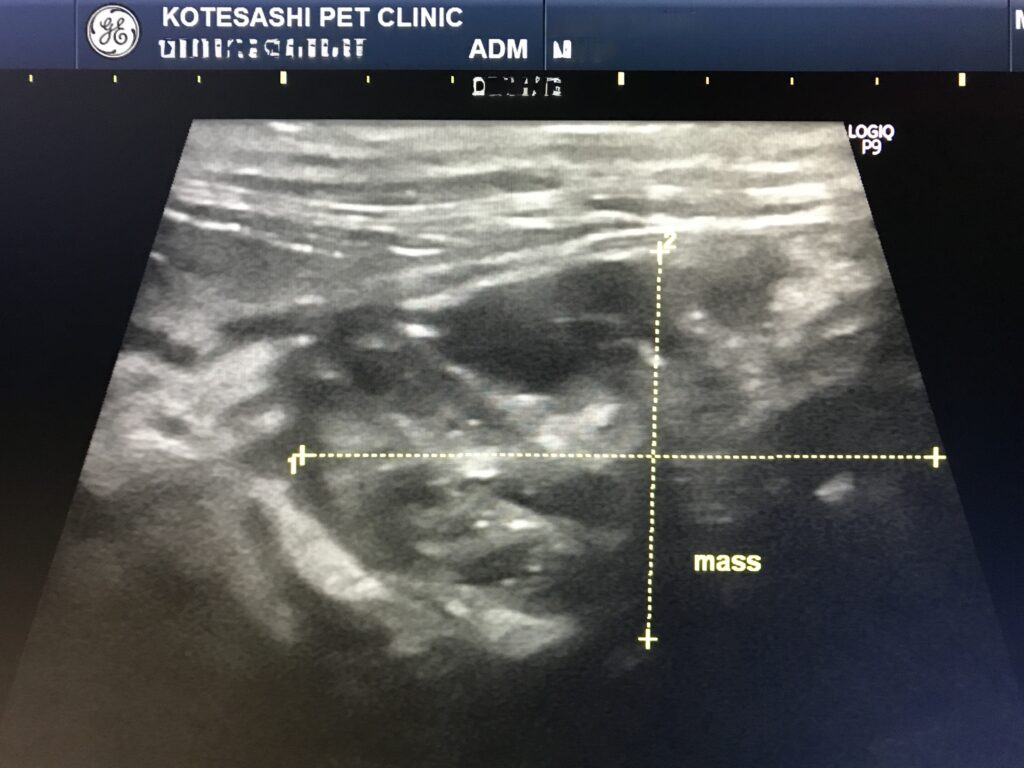

全身の血液検査(生化学検査)では大きな異常がありませんでしたが、エコー検査で消化管腫瘤を確認し、腫瘍又は詳細不明な消化管穿孔と判断し手術を行いました。当時例のように、消化管にシコリがあっても必ずしも血液検査で異常が確認されるわけではありません。

消化管に液体が溜まっている部分と、狭窄(通過障害を起こしている)している部分がありました。

エコー検査で消化管にシコリを認め、リンパ腫の再発と判断